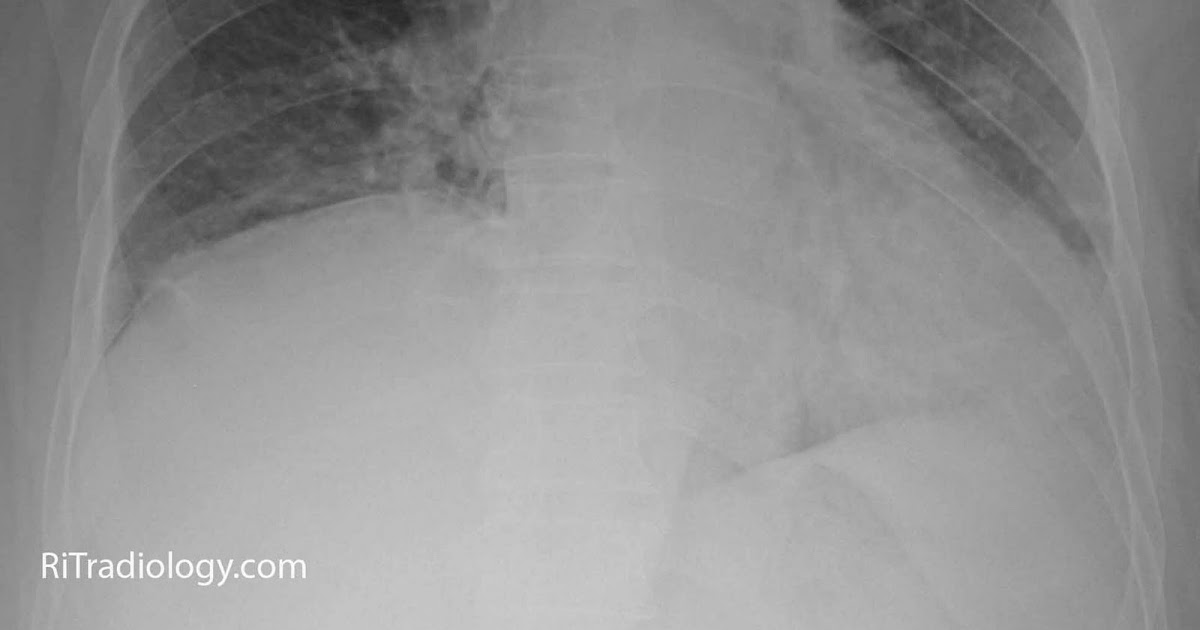

From radiologyinthai.blogspot.com

RiT radiology Unilateral Diaphragmatic Elevation Diaphragm Elevated On Left Side elevated hemidiaphragm is a condition where one portion of the diaphragm is higher than the other. elevated hemidiaphragm is a condition where one portion of the diaphragm is higher than the other. unilateral diaphragm paralysis is often first suspected after the finding of an abnormally elevated hemidiaphragm on a. an elevated hemidiaphragm may result from direct. Diaphragm Elevated On Left Side.

From www.researchgate.net

Chest anteroposterior view radiograph shows elevated left diaphragm and Diaphragm Elevated On Left Side explore the causes, symptoms, diagnosis, and management of an elevated hemidiaphragm, a condition characterized. elevated hemidiaphragm is a condition where one portion of the diaphragm is higher than the other. on the left side, a big stomach filled with food or gas can cause the diaphragm to appear elevated. Up to 90% of unilateral diaphragmatic palsy can. Diaphragm Elevated On Left Side.